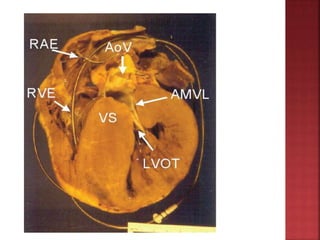

 characterized by thickened but non dilated

left ventricle in the absence of another

cardiac or systemic condition capable of

producing magnitude of the hypertrophy

 Small ventricular cavity and marked

hypertrophy of myocardium with myofibril

disarray w/wo dynamic outflow tract

obstruction

 LV hypertrophy with septum >1.3times

posterior LV wall thickness

 Ground glass appearance of septum

 Spade shaped LV Cavity

 small lv cavity

 SAM of mitral valve

 septal immobility

 premature closure of aortic valve